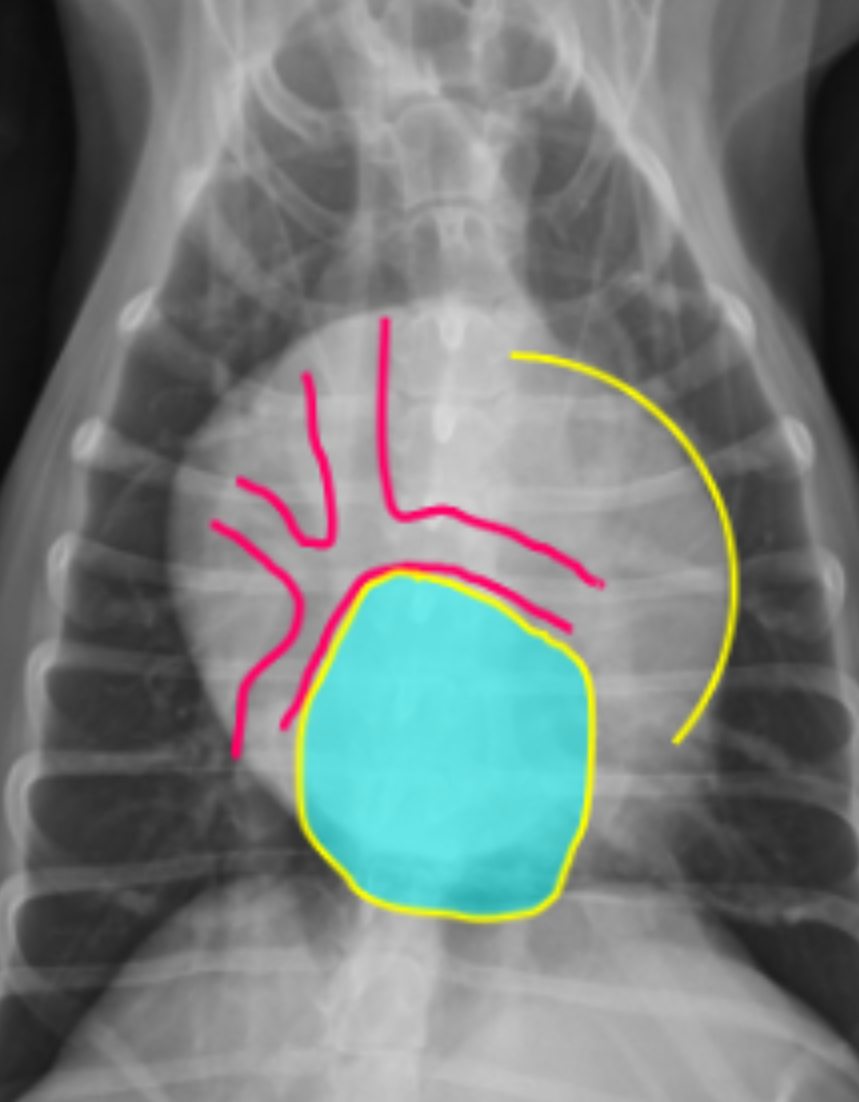

3 features of LVE VD

-elongation of cardiac silhouette

-deviation of apex to the left

-bulge at 3-5 o’clock

What part of the heart is enlarged?

LVE